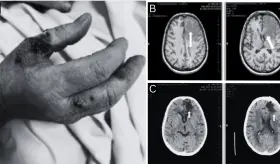

La reactivación ocurrió en el contexto de un aumento en la inmunosupresión, específicamente con el incremento del micofenolato mofetilo (MMF).